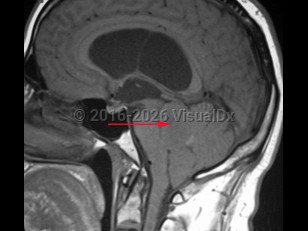

An ependymoma is a tumor of the brain or spinal cord arising from ependymal cells. Ependymomas account for 4% of central nervous system (CNS) tumors in adults and 10% of CNS tumors in children. In children, they are most often located in the 4th ventricle and posterior fossa, whereas in adults, they are more frequently located in the spinal cord. In the spinal cord, they tend to occur centrally, causing symmetric cord expansion. Peak incidence in adults occurs between 30 and 40 years of age.